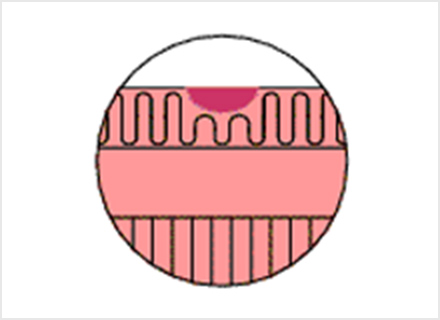

炭酸ガス送気

通常、内視鏡の検査では胃や大腸に空気を入れて膨らませながら検査をするため、検査の後のお腹のハリが苦痛となります。 当院では、患者さんの苦痛が少しでも和らぐように、空気より100倍以上早く水分に吸収される、炭酸ガス送気を導入しています。